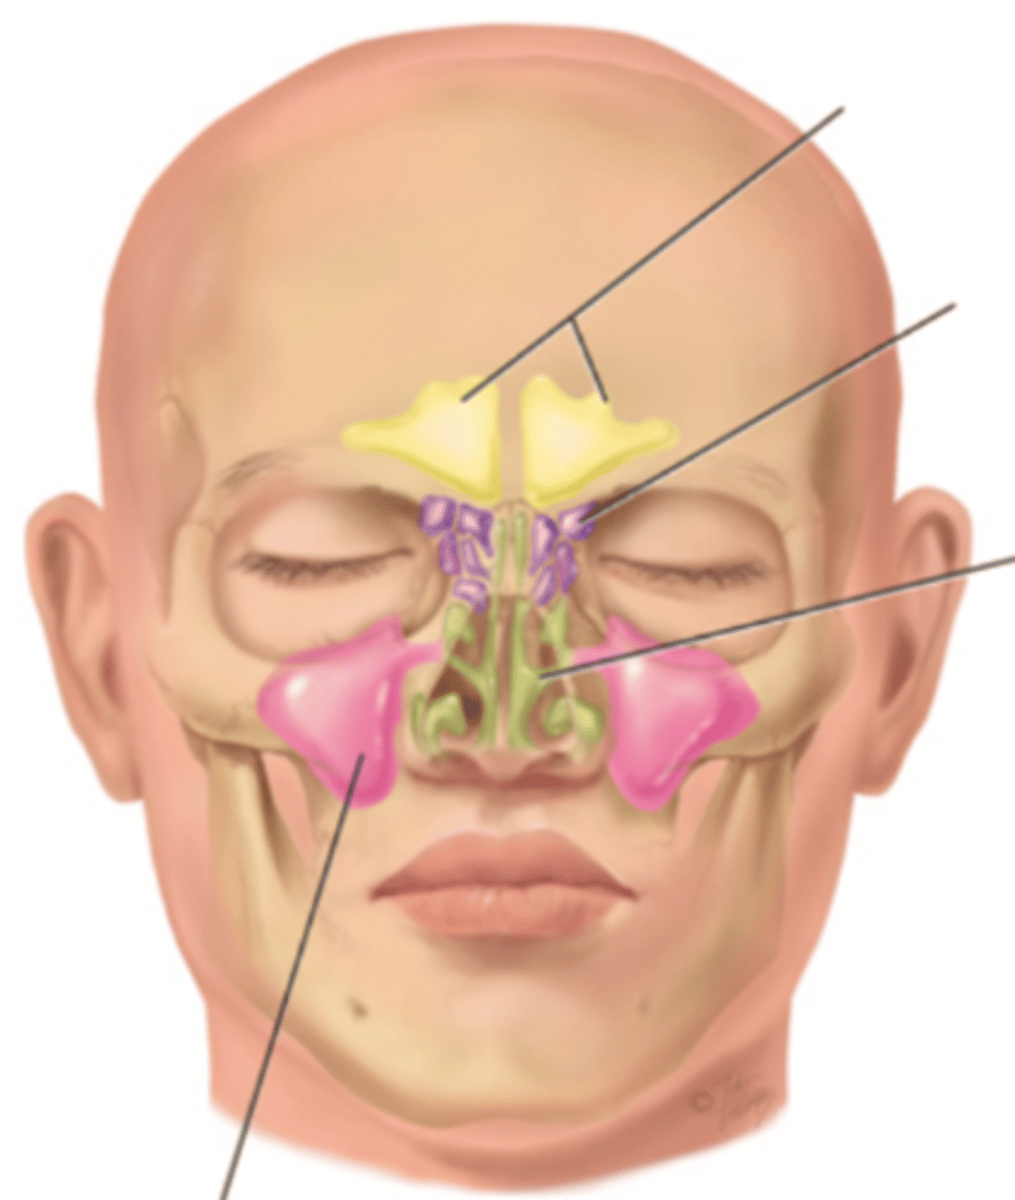

Paranasal Sinuses

- Frontal

- Ethmoid

- Sphenoid

- Maxillary

Frontal Sinus

Cavity within the frontal bone (yellow)

Ethmoid Sinus

Mucosa lined air spaces located above the sphenoid sinus and below the frontal sinus (purple)

Sphenoid Sinus

Sinus above and behind the nose (green)

Maxillary Sinus

Sinus on either side of the nasal cavity below the eyes (pink)